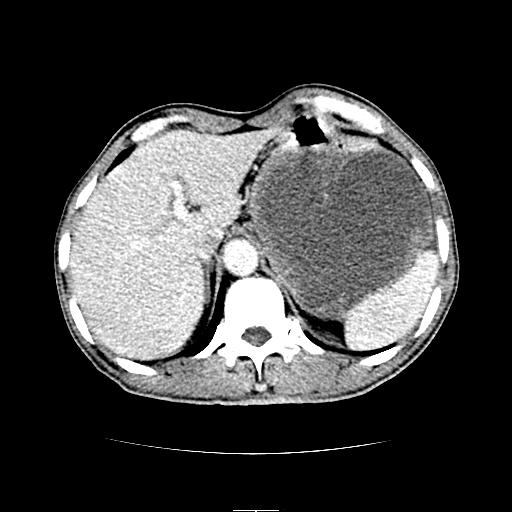

左上腹胃、脾及胰腺间巨大囊性占位性病变,内见多数薄隔,有轻度强化,明显占位效应。左肾见一小囊肿。

左上腹胃、脾及胰腺间巨大囊性占位性病变,内见多数薄隔,有轻度强化,明显占位效应,胰腺及左肾结构清楚,明显向后下方推压 移位。左肾见一小囊肿.多考虑:1 网膜巨大囊肿。2 左肾小囊肿。

1胃脾胰之间一巨大囊性影,胃明显向前推移,胰体尾部似肥大,考虑囊性影来源于胰腺(假性囊肿?)2左肾小囊肿。

胃脾胰之间一巨大囊性影,内可见间隔,应为囊实性占位:多考虑:1 网膜巨囊腺瘤?。2 左肾小囊肿

跟胰腺关系不大,肿物在胰腺后上方。考虑胃间质瘤或小网膜囊原发肿瘤。